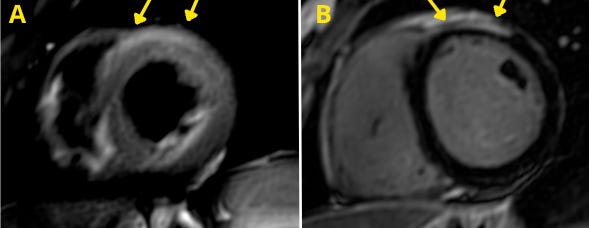

Imagem da Semana

Caso de miocardite aguda avaliado pela ressonância magnética cardíaca e que cumpre os critérios de Lake Louise: presença de hiperssinal em sequência ponderada em T2 (A) + realce tardio subepicárdico no segmento anterior (B).